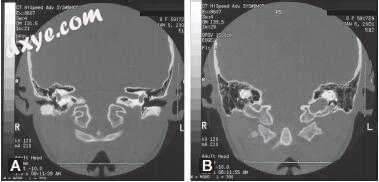

图-7. 颞骨骨扫描计算机断层扫描与Bezold脓肿患者的对比。 A,外耳道和中耳的不透明(白色箭头)。 还要注意乳突下部(黑箭头)的骨质破坏。 B,在茎突的根部(白色箭头)水平切割得更差,表明乳突尖端前部(黑箭头)的骨头破坏。 C,软组织开窗显示Bezold脓肿,在乳突尖端水平增强囊(箭头)。 D,可见脓腔(箭头)在颈部向下延伸至舌骨水平(箭头)。